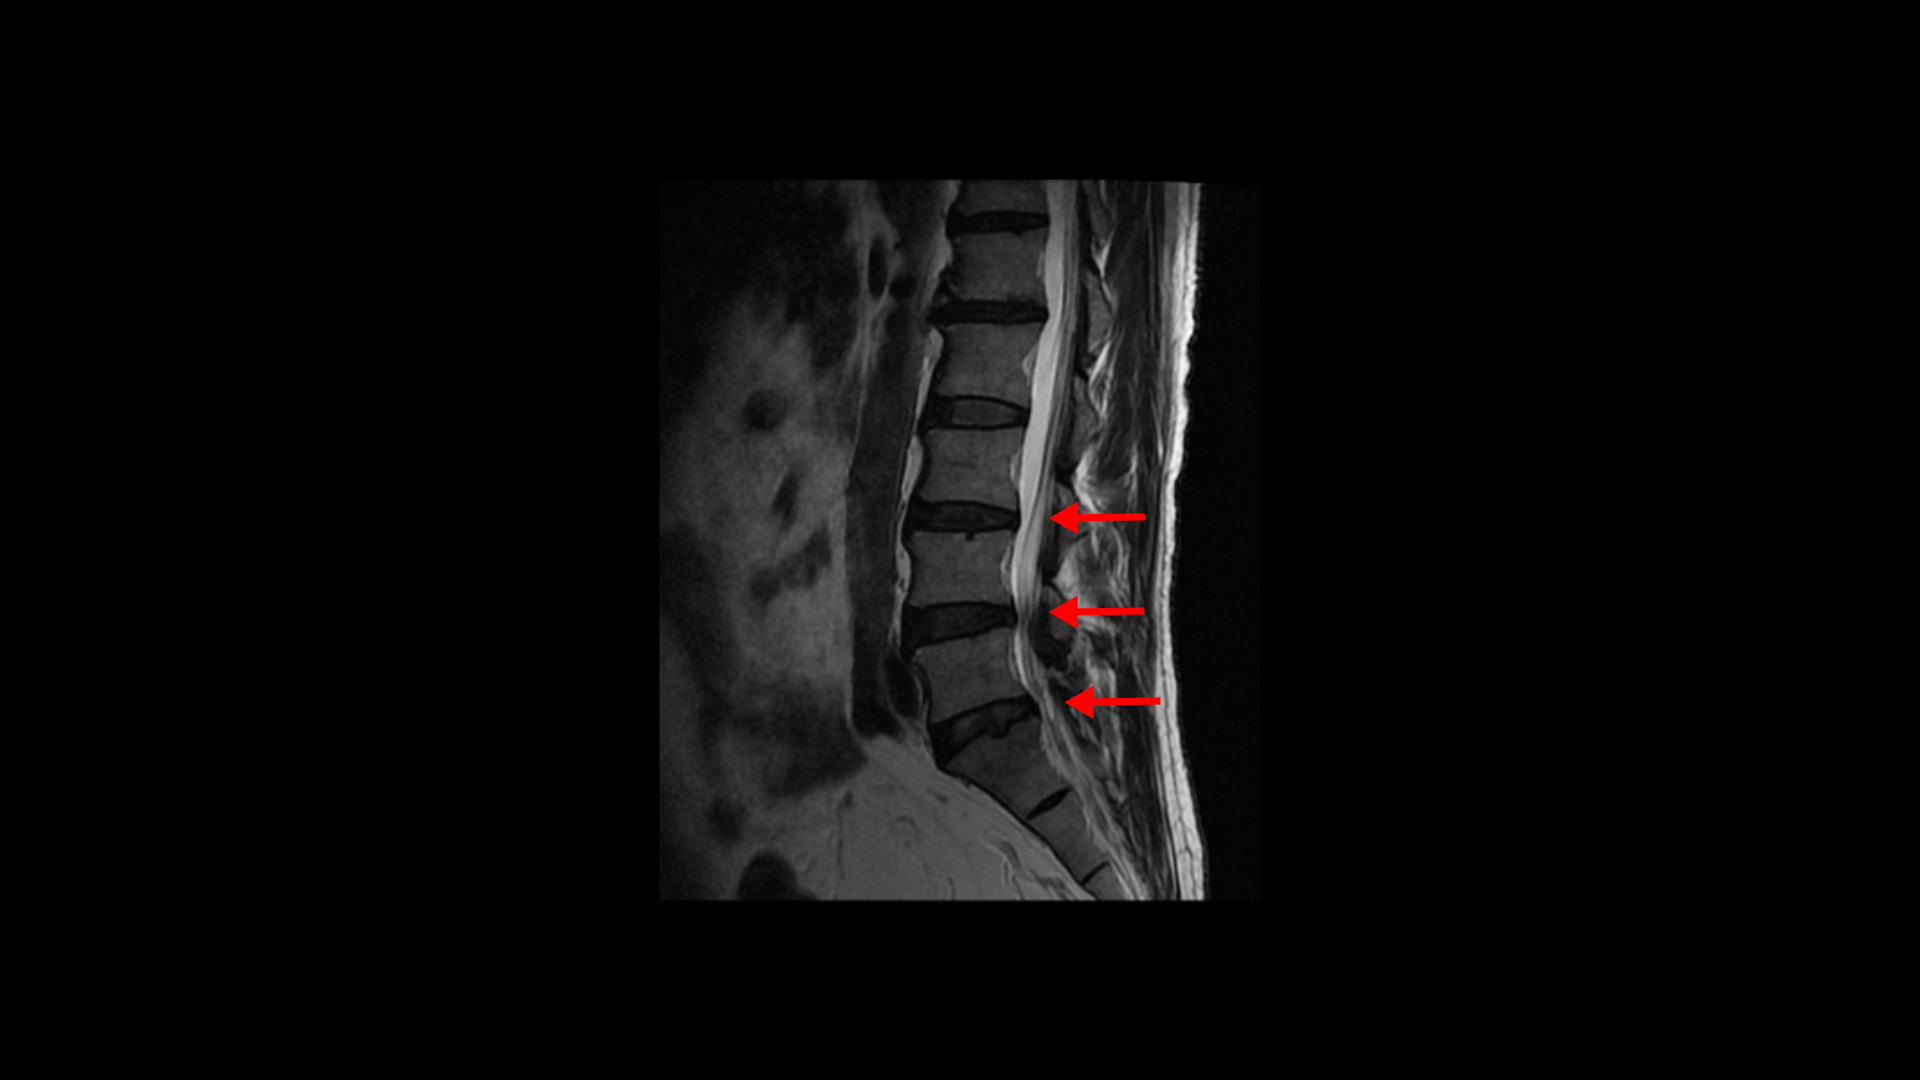

특히 MRI에서 보이는 신경 눌림이 심하지 않을수록 근육 문제일 가능성은 훨씬 더 높아집니다. 이 환자분 MRI를 한번 볼까요? 세 마디에 퇴행성 디스크가 있지만 심하지 않습니다.

4번 5번 마디의 척추관도 협착이 진행되었지만 좁아진 게 많이 심하지 않습니다.

오른쪽, 왼쪽 신경이 빠져나가는 추간공도 조금 좁아지긴 했지만 별로 심하지 않습니다.